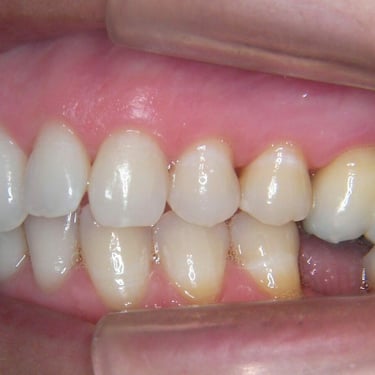

Pérdida de múltiples dientes

La pérdida de múltiples dientes es la ausencia de varios dientes que puede ser resultado de caries, enfermedades periodontales o traumatismos.

Los pacientes notan varios espacios vacíos en su boca, lo que afecta su capacidad para masticar y hablar adecuadamente.

El tratamiento incluye la colocación de varios implantes dentales para restaurar la función y la estética.